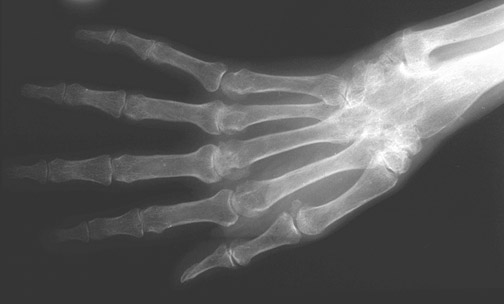

This hand demonstrates changes of rheumatoid arthritis. There is joint narrowing with marginal erosions and osteoporosis, mainly involving the

proximal interphalangeal (PIP) joints

and

metacarpophalangeal joints

.